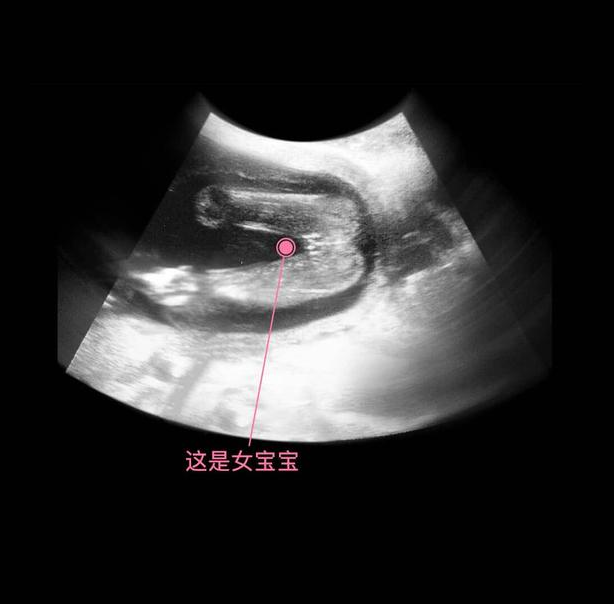

其实从孕9周开始,胎儿的性别就开始分化,孕17周,B超扫描清晰可见胎儿的性别,不过也有的宝宝因为胎位的原因,或者脐带遮挡,让医生产生了误判,男女会出现翻盘的可能呢。